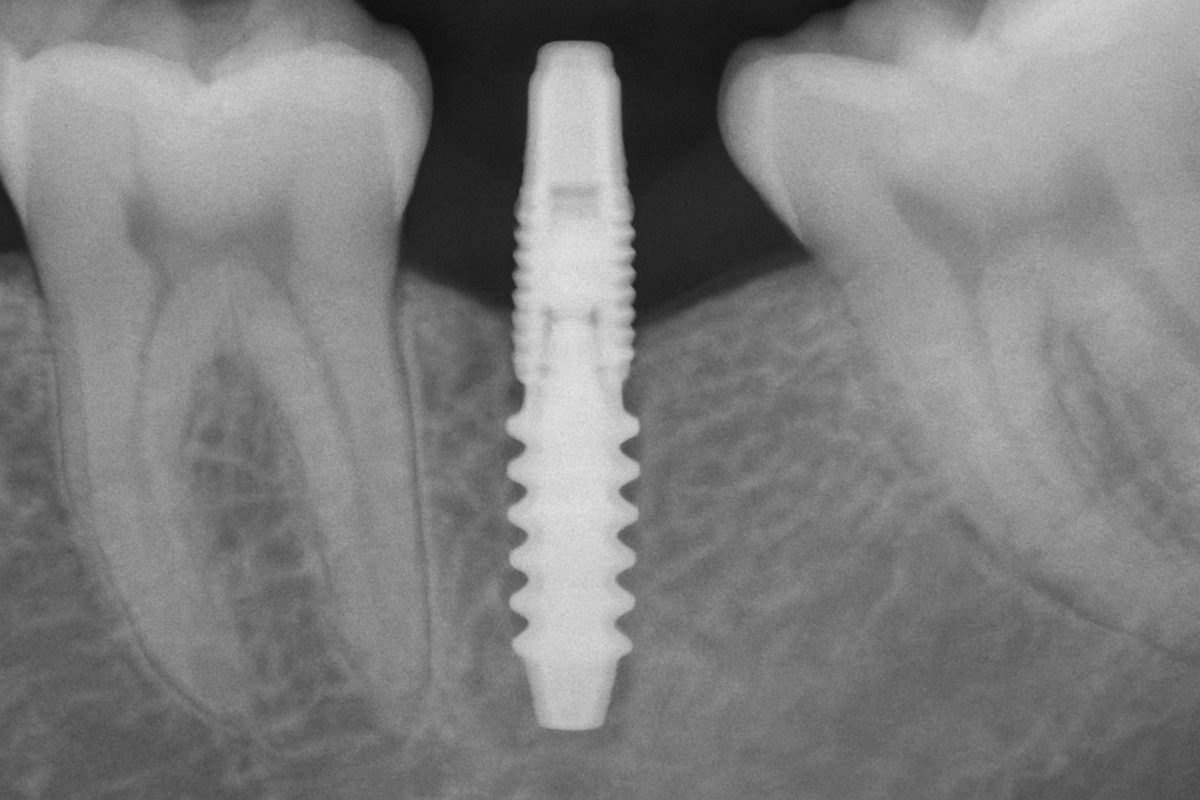

Dental implants in St. Louis are a permanent way to replace missing teeth. If you’re tired of loose dentures, gaps, or limits on what you can eat, dentistry implants may be the solution. This post explains what dentistry implants are, who should consider them, the benefits, the step-by-step process, potential risks, typical costs and financing, […]